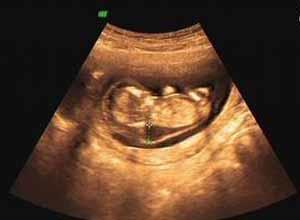

简介水囊瘤(hygroma)又称先天性囊状水瘤、囊状淋巴管瘤(cystic lymphangioma)是来源于淋巴组织的先天性疾病可发生于身体各部,但以颈部最常见。多为柔软、有波动感、无痛的肿物,不易被压缩,透光好。药物囊内注射治疗效果好、安全、方便,是临床治疗首选。是新生儿及婴儿的常见病,约在新生儿期即已发生,因体积小无明显临床表现而被忽视。90%以上患者在2岁内发现。男女发病率基本相似。水囊瘤的75%发生于颈部,其余依次为腋下、胸壁纵隔、腹膜后、盆腔和腹股沟等大网膜囊肿及肠系膜囊肿亦属水囊瘤。水囊瘤虽属良性病变,但可向周围组织甚或主要器官浸润生长,有可能在短时间内出现危及生命的并发症因此大多数水囊瘤均应积极治疗若病变较小,确无任何症状的患儿可随诊观察1~2年。